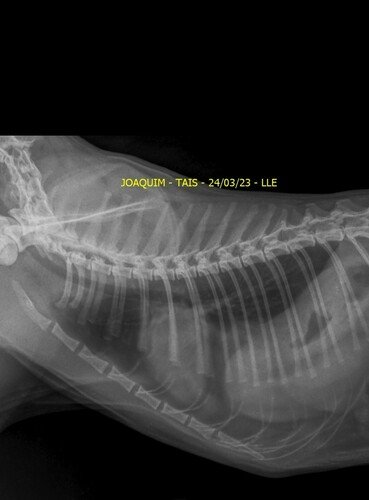

Venha aqui pedi ajudar de vocês. Meu gato, o Joaquim,sofreu um acidente no dia 14/03. Ele rompeu o diafragma e precisa de uma cirurgia urgente. Está com problema respiratório, teve umas lesões interna, uma lesão na pata traseira e não come devido o rompimento. Ele precisa fazer essa cirurgia o mais rápido possível.